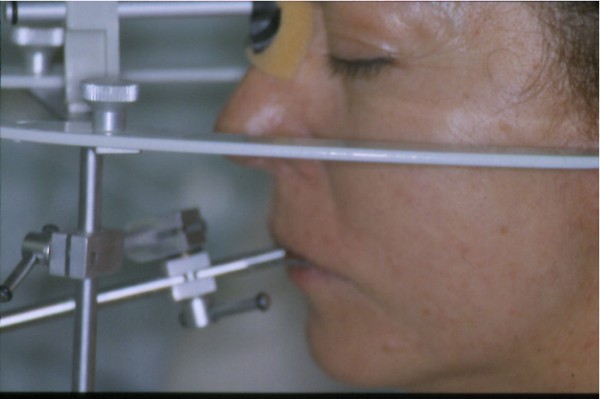

Entidades patológicas como el bruxismo, limitan la terapéutica odontológica y las certezas de un pronóstico favorable y prolongado en el tiempo. El strees, factor predisponente, y alteraciones morfológicas en la oclusión que impiden la disclusión de los sectores posteriores durante las excursiones de la dinámica mandibular, o factores desencadenantes. Caso Clínico Mujer , 53 años, derivado por especialista en Cirugía Máxilo Facial, con evidentes signos de hipertrofia de ambos maseteros. Clínicamente la carencia de las puntas caninas de ambos lados de ambas arcadas, nos habla de ciclos masticatorios eminentemente horizontales, tipo rumiante, donde el fenómeno de DOBLE DESGASTE de las cúspides estampadoras se pone en clara evidencia.(Fig.3 y 4 ) Ambos fenómenos(desgaste exagerado y extrusión dentaria nos habla de una invasión del espacio del maxilar superior, mediante la elevación del inferior, con las lógicas consecuencias musculares por acortamiento: Hipertrofia, acúmulo de ácido láctico, sobrecarga de los elementos tendinosos y capsulares, etc. Se le hace saber al paciente acerca de la necesidad de múltiples técnicas de Rehabilitación ANTES de llegar a reponer sus piezas perdidas. Se le pone en conocimiento de la necesidad de reponer SOLO hasta su primer molar, el que se reemplazará mediante una PREMOLARIZACIÓN, dado que el ancho de su cresta no permite reemplazar un primer molar salvo con riesgos de invadir el ESPACIO BIOLÓGICO necesario para un buen desarrollo de sus funciones. Es necesario tener en cuenta, que la pérdida de dimensión vertical por excesivo desgaste de la porción coronaria es siempre acompañada, por un descenso de las estructuras corticales, desfavoreciendo la relación CORONO/RADICULAR, lo que hace fundamental el ejercicio de unas fuerzas oclusales VERTICALES, a fin de no aumentar la movilidad de las piezas, una vez que la altura adecuada haya sido restablecida, verticalidad que solo se alcanzará mediante la implementación de una GUÍA ANTERIOR adecuada. Se estudia el caso clínicamente y se toman modelos de estudio debidamente montados en articulador semi ajustable en posición de ORC que es la única posición posible para rehabilitar, sin incurrir en alteraciones posicionales de la ATM, ni de elongaciones musculares y tendinosas que generen una nueva situación de strees muscular y empujen al sistema al bruxismo. Se analizan los modelos en forma estática y dinámica, donde se observan no solo las facetas parafuncionales de desgaste sino también la carencia de disclusión canina, patología generadora de dichas facetas, y que, Se confecciona un Encerado de Diagnóstico(Fig.A/B) a partir del cual se tallan las piezas en los modelos y se reproduce un juego completo de provisionales a utilizar durante el procedimiento clínico. (fig. 9) Se realizan las endodoncias y se refuerzan con Pernos Muñones Colados en oro, mediante los conceptos de Alineación Tridimensional correspondientes, instalándose los provisionales efectuados a partir del encerado de diagnóstico, los que cumplen con la tarea de discluir los sectores posteriores , tal como se concibió en dicho encerado.(Fig.10-11-12-13-14) Transcurridos seis meses de control, donde se verifican las funciones del sistema, dentro de un marco adecuado de ortofunción en el cual tal vez el más importante índice es el escaso desgaste de los provisorios, los que funcionan en una adecuada OCLUSIÓN en RELACIÓN CÉNTRICA y DIMENSIÓN VERTICAL ,situación esta apoyada por la presencia nocturna de una férula de Relajación, donde podemos observar y además «escuchar» al enfermo decirnos de su mejoría masticatoria y de la desaparición del «estado de agarrotamiento» que sentía en la boca al despertar, verificando que se siguen produciendo las disclusiones adecuadas en todas las excursiones mandibulares. Realizamos entonces al estudio radiológico adecuado, procediendo a instalar ocho(8) implantes roscados, tres de los cuales son insertados con una ligera elevación de ambas mucosas sinusales intra alveolarmente.(Fig.15-16-17) Transcurridos tres meses más y verificando la correcta cicatrización tomamos impresiones para realizar los abuttments de oro correspondientes, sobre los que instalamos un nuevo juego de provisionales que ya dan carga a los implantes.(Fig.18-19-20-21-22) Ahora estamos en presencia de un Sistema Estomatognático que presenta las características idoneas para funcionar, características estas que observamos permanentemente sobre todo la función de la GUIA ANTERIOR. Recién entonces confeccionamos las Restauraciones Periféricas Totales, las que serán realizadas en Porcelana sobre Oro . Se procede entonces a la confección de los sectores posteriores constituidos en este caso por tres premolares en cada hemiarcada de cada maxilar.(Fig.29-30) Se constatan la Estética, el Ajuste Cavo Superficial, El Espacio Libre Interoclusal, la Dinámica Mandibular,etc.(31-32-33-34-35-36-37-38-39-40) Evidentemente un caso exitoso no muestra las bondades de un método. Sin embargo, la casuística popular acerca de la imposibilidad de ser implantados aquellos pacientes que padecen bruxismo es tan frecuente como realizar en bruxómanos, coronas totales con oclusal metálica a fin de no permitir que las fuerzas de la oclusión destruyan nuestro «trabajo, sin tener en cuenta que no es la dureza del metal quien evita la destrucción…. BIBLIOGRAFÍA: 1-Oclusión y Diagnóstico en Rehabilitación Oral. 2-Disfunción temporo Mandibular y Equilibración Oclusal. 3-Rehabilitacion Bucal. 4-Problemas Oclusales. 5-Oclusión. 6-Oclusión. Conceptos para el Clínico. 7-Disfunción temporo Mandibular. 8-Neurofisiología de la Oclusión. 9-Gnatología.Principios y Conceptos.José dos Santos. 10-Oclusión y Rehabilitación. 11-Procedimientos Clínicos y de Laboratorio de la Oclusión Orgánica.

Estando satisfechos de la misma, realizamos un nuevo montaje en articulador RESPETANDO LA ORC QUE DICHA GUIA NOS OFRECE y que hemos observado continuamente.(Fig 23-24)